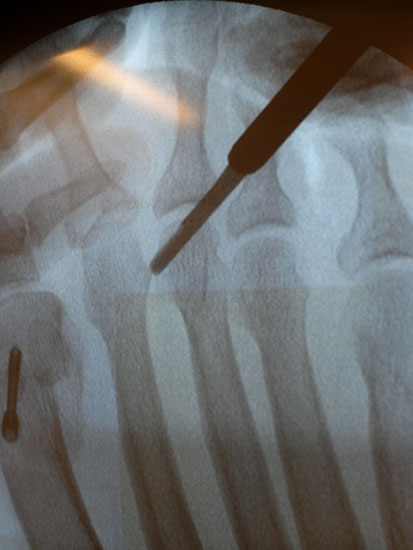

Nach Bestimmung der korrekten Osteotomiehöhe wird mit dem MIS-Mikrotom eine je nach Seitendominanz des Operateurs dorsolaterale oder dorsomediale 3-4mm lange Längsinzision parallel zu den Strecksehnen auf Höhe des metadiaphysären Überganges am distalen, zu osteotomierenden Metatarsale  durchgeführt. Im Anschluss erfolgt die Präparation mit einer schlanken, im Schaft gebogenen und vorne stumpfen Raspel oder mit einem gebogenen Klemmchen. Die Präparation erfolgt unter stetigem  Knochenkontakt mit der Kortikalis des Metatarsale medial oder lateral bis nach plantar unter die Beugesehenen.  So kann der Weg für die Fräse vorpräpariert und eine Weichteilinterposition zwischen Fräse und Knochen vermieden  werden.

Jetzt erfolgt das Einbringen der Fräse im 45°-Winkel von distal dorsal nach proximal plantar. Auf steten Knochenkontakt mit der Kortikalis zur Vermeidung eines Weichteilinterponates sollte geachtet werden. In unserer Abteilung erfolgt vor Beginn der Osteotomie nun eine nochmalige Lagekontrolle der Fräse unter dem Bildwandler im dorsoplantaren Strahlengang. Eine zusätzliche laterale Aufnahme kann die Tiefe der eingebrachten Fräse in Bezug auf das zu osteomierende Metatarsale zeigen, ebenso ermöglicht sie eine Kontrolle des 45°-Winkels.